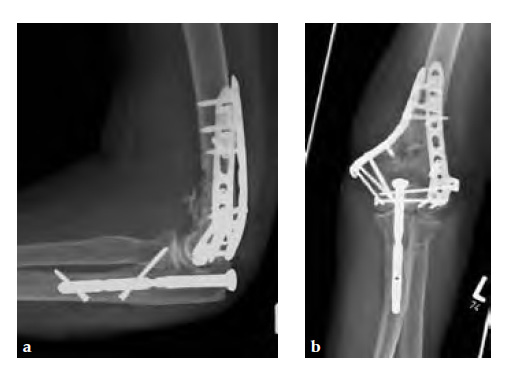

The nail is inserted through a triceps tendon longitudinal split of approximately 1 cm. The entry portal is predrilled and the distal part of the nail is inserted at a position distal to the location of the osteotomy using an insertion handle. The implant is cross locked prior to creating the osteotomy. After the distal humerus is fixed, the osteotomized tip of the olecranon is brought back to its original position and an end cap is inserted through the predrilled hole in line with the nail, reducing the olecranon and creating compression across the osteotomy, ensuring an anatomical reduction/alignment. This procedure allows for a quick and easy realignment and fixation of the olecranon. The locking holes in the distal part of the nail are oblique to each other as well as to the anatomical axis of the ulna. This design prevents the nail from moving within the medullary canal to prevent toggling and ensures anatomical reduction of the olecranon fragment. Targeted locking minimizes the size of the incision. The threaded head of the locking screws sit flush with the surface of the ulna minimizing hardware prominence and soft tissue irritation.

Overall, the olecranon nail system provides more stable fixation with less overall fracture gap motion compared to alternative fixation techniques. Since the implant is inserted prior to the osteotomy, refixation of the olecranon at the end of the procedure is an easy and quick procedure.

A 75-year-old female pedestrian was hit by a car and sustained a 2 open fracture of the distal humerus and an additional pelvic ring fracture.

Case provided by Martin Hessmann, Fulda, Germany